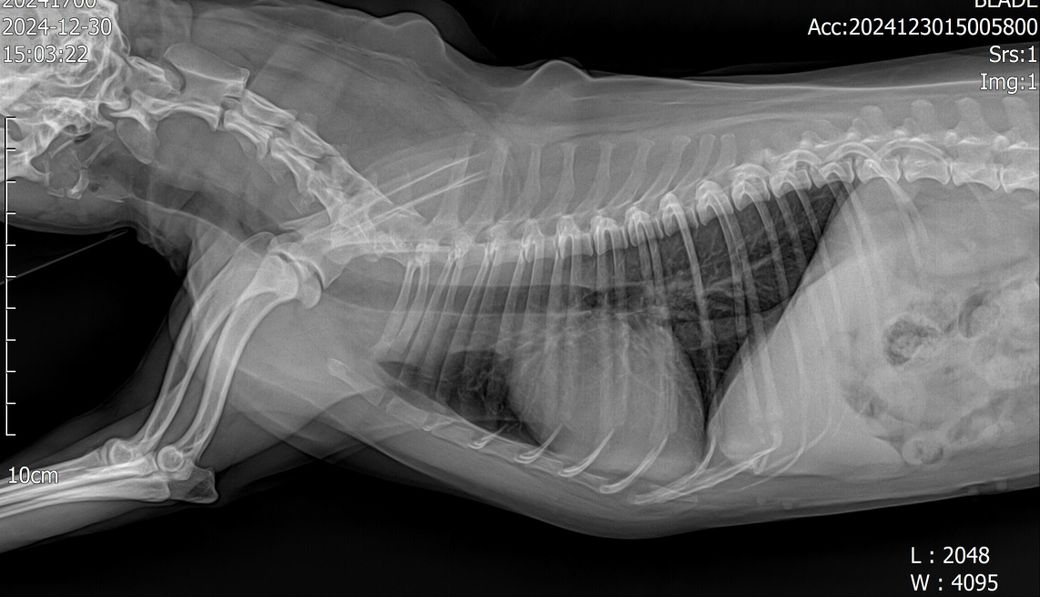

강아지 폐 기관지 엑스레이 좀 봐주세요

안녕하세요 어디서는 섬유화가 진행중이라고하고 3일뒤 다른병원가서 다시찍으니 만성기관지염이라고하네요 엑스레이 좀 봐주세요 ㅠㅠ기침은 하루에 켁켁켁카악 이걸 한번으로치면 3번정도는 해요 기본 한두번은 항상하구요

방사선 검사에서 초기 폐섬유화증은 만성 기관지염과 동일한 소견을 보입니다. 그래서 실제 조직검사를 하기 전까즈는 폐섬유화증고 만성기관지염은 방사선 검사를 통해 감별할 수 없습니다.

또한 만성 기관지염이 진행되면 시간이 흐르면 폐섬유화증이 동반되기 때문에 엄격하게 이 둘을 구분하는것은 초기인 경우 큰 의미는 없습니다.

또한 폐 섬유화증이 진행하여 임상증상이 발현하는 빈도는 매우 낮고 만성기관지염은 이보다 훨씬 잦게 나타나는 현상으로 둘을 구분하기보다 만성 기관지염으로 가정을 하고 치료하는게 옳은 선택입니다.

첨부한 사진에서 세기관지벽의 침윤 양상과 함께 무정형의 간질성 침윤이 동반되어 있기 때문에 일차적으로 만성 기관지염이 있을 가능성이 매우 높고, 이 사항이 충분히 관리되지 않으면 향후 폐섬유화증으로 진행될(혹은 일부 진행된 상황) 가능성을 고려해야 하니 두 동물병원의 소견이 모두 맞다고 볼 수 있습니다.